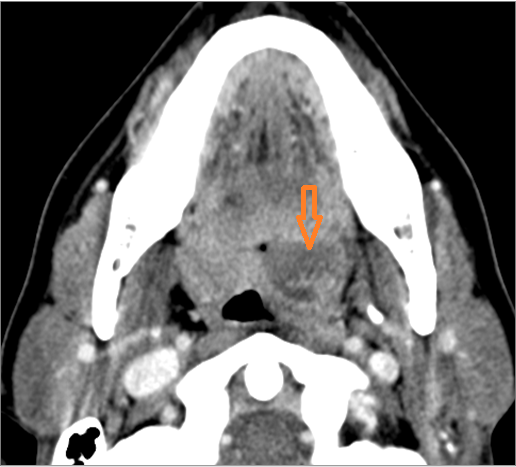

There is edema or abscess within the fat of the adjacent parapharyngeal and retropharyngeal space. [Yes/No]

There is edema or abscess within the adjacent parapharyngeal and retropharyngeal spaces. [Yes/No]